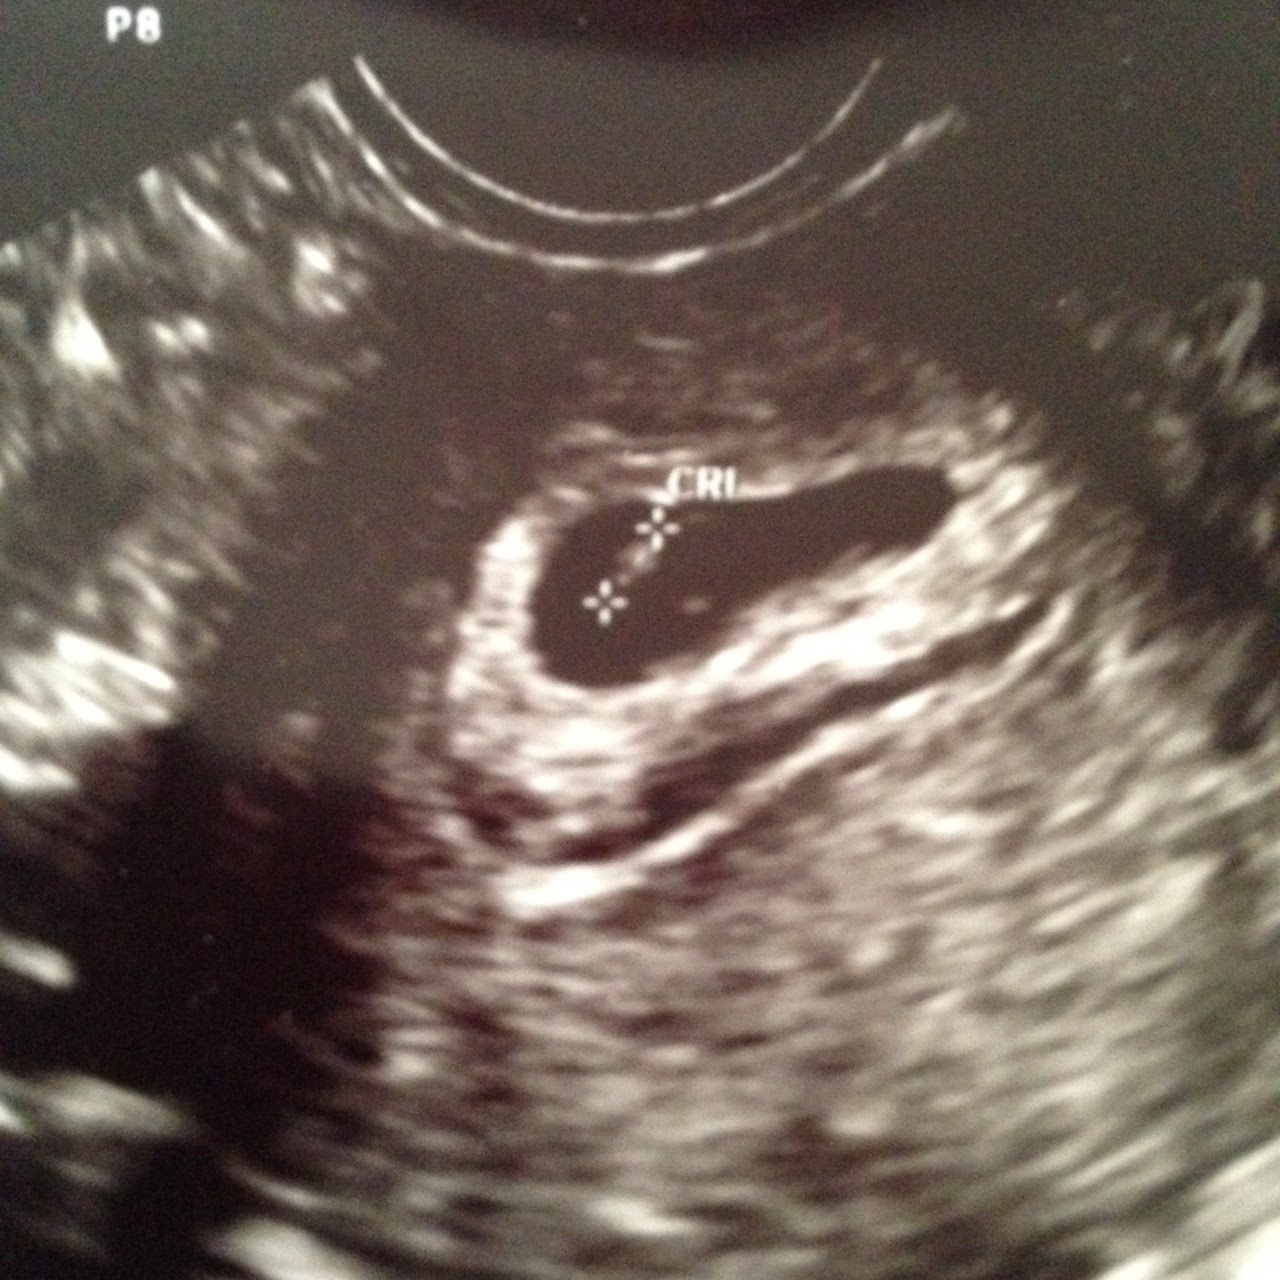

Subchorionic hematoma Υποχοριονικό αιμάτωμα Ultrasound cases YouTube

Subchorionic hematoma Υποχοριονικό αιμάτωμα Ultrasound cases YouTube Subchorionic Hematoma Heating Pad In this episode, we'll talk about exercise,. Subchorionic hemorrhage occurs when there is perigestational hemorrhage and blood collects between the uterine wall and the chorionic membrane in pregnancy. A subchorionic hematoma is when blood collects under the chorion membrane during pregnancy. A subchorionic hematoma or hemorrhage is bleeding between the wall of the uterus and one of the sacs (chorion). Subchorionic Hematoma Heating Pad.

Subchorionic hemorrhage Image Subchorionic Hematoma Heating Pad A subchorionic hematoma or hemorrhage is bleeding between the wall of the uterus and one of the sacs (chorion) that surrounds the embryo. In this episode, we'll talk about exercise,. Subchorionic hemorrhage occurs when there is perigestational hemorrhage and blood collects between the uterine wall and the chorionic membrane in pregnancy. A subchorionic hematoma is when blood collects under the. Subchorionic Hematoma Heating Pad.